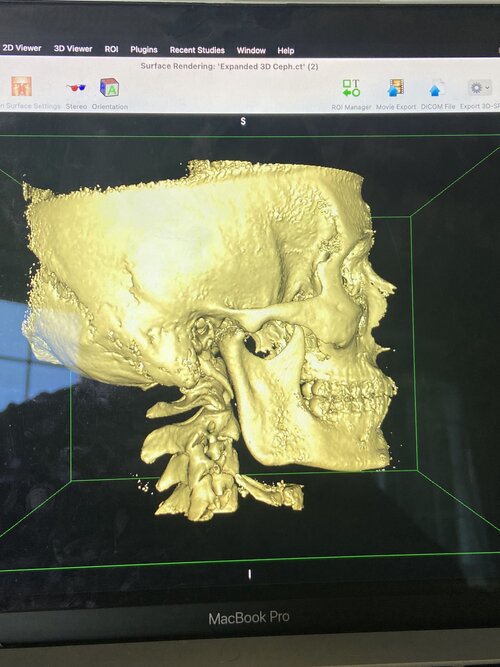

lets look at the bones:

lets look at the bones: